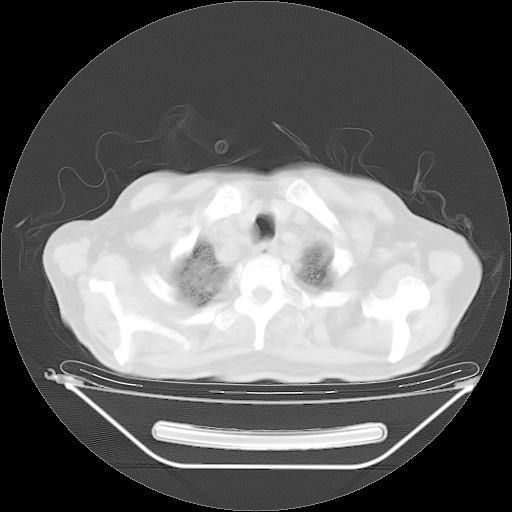

5月9日肺部CT(在4月27日齐鲁医院肺部CT描述部分肺组织磨玻璃样改变,12天后肺组织广泛磨玻璃样改变)

2009年5月9日肺部CT

大致读了系列胸部CT:纵隔窗无明显异常,肺窗:从4、27至今:主要是双肺中下野外带可见毛玻璃样改变,目前处于急性肺泡炎阶段,至于原因考虑1、结替组织或胶原血管性疾病所致?2、恶性疾病如恶组在肺部所致的表现或细支气管肺泡癌?3、药物或其它原因如肺蛋白沉着症所致肺泡炎目前不太可能?总之,明天就去请我院的呼吸科、感染科、血液科和临免专家会诊哈。